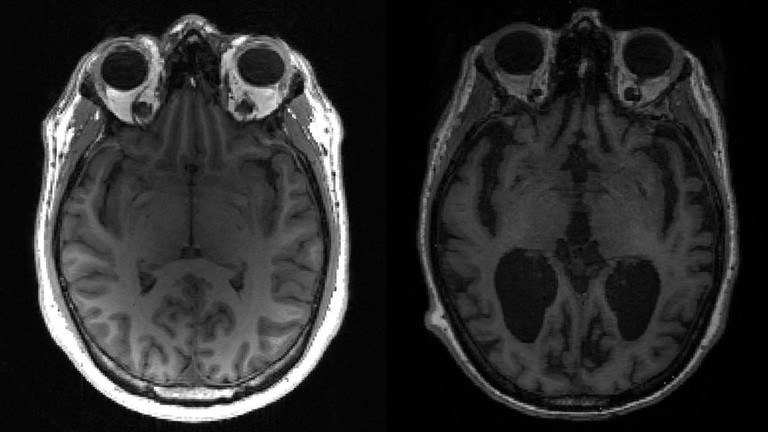

The eastern European country of Slovenia a person purporting to be a whistleblower nurse named Vera Kanalec claims that politicians and other high ranking citizens receive saline placebos instead of the mRNA experimental medication.

In a video on Facebook, the woman claiming to be the *head nurse of the University Medical Center in Ljubljana, which takes care of receiving and managing the jab bottles...